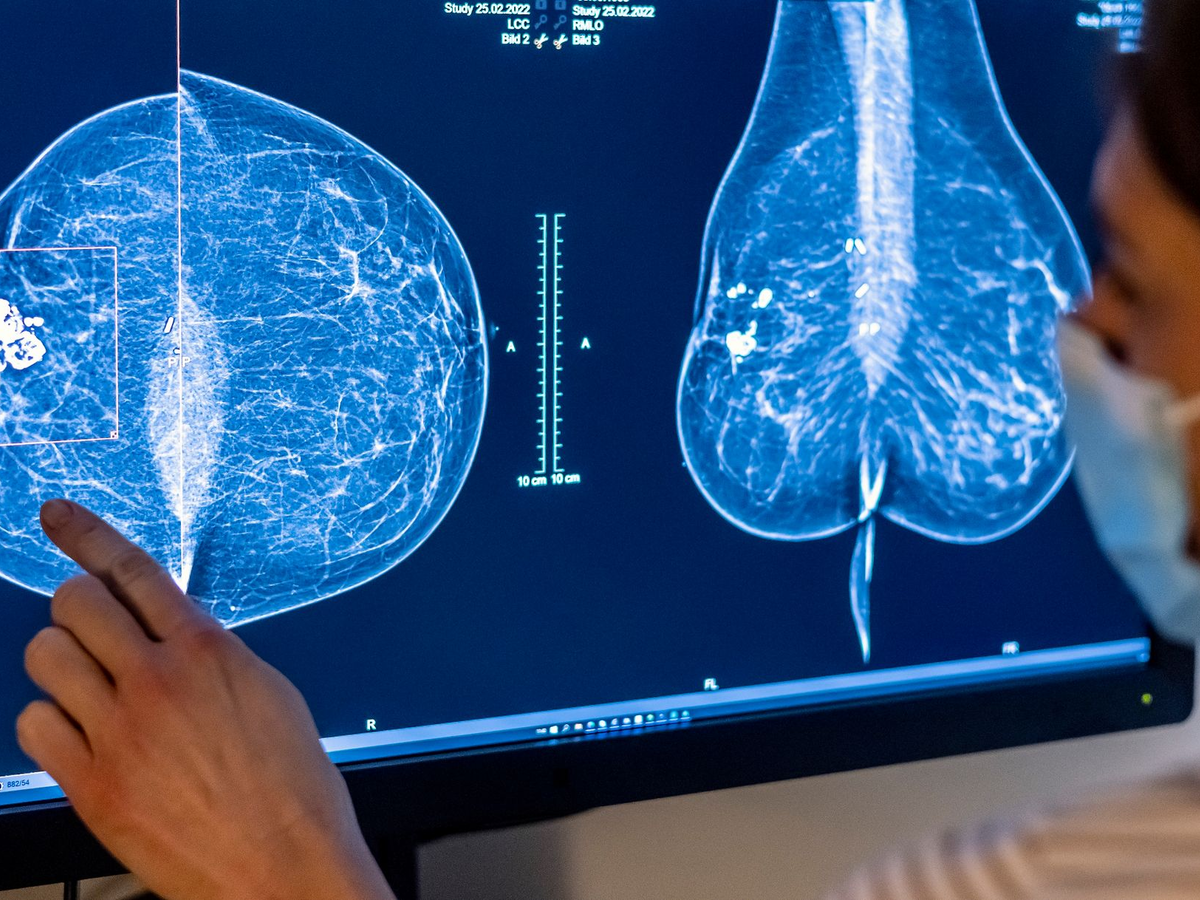

Untersuchungen zur Brustkrebsfrüherkennung bei Frauen sollten nach einem Expertenbericht früher als bisher beginnen. Es werde empfohlen, die untere Altersgrenze von 50 auf 45 Jahre herabzusetzen, teilte das Bundesamt für Strahlenschutz (BfS) mit. Nach Angaben der Forschungsbehörde mit Sitz im niedersächsischen Salzgitter ist das Mammographie-Screening-Programm auch für Frauen ab 45 Jahren mit mehr Nutzen als Risiken verbunden.

Der Bericht zeige, dass das Screening die Sterblichkeit an Brustkrebs auch bei jüngeren Frauen senken könne, sagte BfS-Präsidentin Inge Paulini. «Er belegt außerdem, dass das damit verbundene Strahlenrisiko relativ gering ist», sagte sie zu der neuen Empfehlung. Brustkrebs ist laut BfS-Angaben die häufigste Krebserkrankung bei Frauen. In der Altersgruppe zwischen 45 und 50 Jahren erkrankten demnach in Deutschland jedes Jahr etwa 5000 Betroffene.

Seit 2009 wird Frauen zwischen 50 und 69 Jahren alle zwei Jahre eine Röntgen-Untersuchung zur Früherkennung angeboten. Ab diesem Sommer dürfen nach einer novellierten Verordnung des Bundesumweltministeriums Frauen bis zur Vollendung ihres 76. Lebensjahres an dem Screening teilnehmen. Zusätzlich rund 2,5 Millionen Frauen sollen davon profitieren. Das BfS hatte diese Ausweitung der Altersgrenzen nach eigenen Angaben bereits 2022 geprüft und befürwortet.

Für den aktuellen «Brustkrebsfrüherkennung mittels Röntgenmammographie bei Frauen unter 50 Jahren» seien acht Studien, die hohen wissenschaftlichen Anforderungen genügen, aus vier Ländern ausgewertet worden. In die Analyse flossen demnach Daten von rund 370 000 Frauen im Alter von 39 bis 49 Jahren ein. Die Analyse komme zu dem Ergebnis, dass das Screening die Brustkrebssterblichkeit in der jüngeren Gruppe in einem ähnlichen Maß wie in der Gruppe der 50- bis 69-Jährigen reduzieren kann, also um rund 20 Prozent.